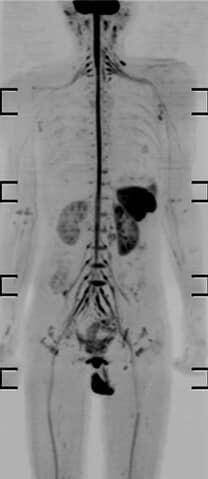

La gran ventaja: difusión 3D (Pseudo PET)

Una de las características más importantes de esta prueba es la secuencia de difusión en 3D.

Esta técnica permite:

- Mapear el cuerpo completo

- Buscar metástasis

- Detectar lesiones ocultas

El nombre técnico es Pseudo PET-TAC.

Traducido al lenguaje del paciente:

Es una prueba muy parecida al PET, pero sin inyectar isótopos radiactivos.

Esta es una de las razones por las que la resonancia magnética de cuerpo entero está creciendo tanto en los últimos años.